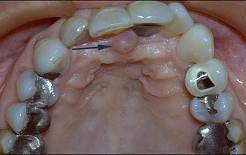

问题 无牙颌患者的口内特征为()

选项 A.牙列缺失 B.牙列缺损 C.牙冠缺损 D.牙体缺失 E.牙体缺损

答案 A